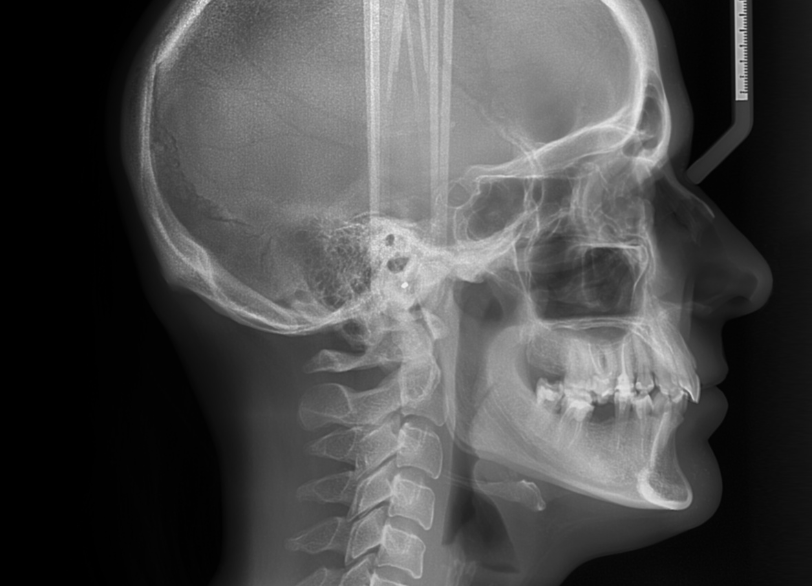

セファロレントゲン

主に矯正治療の診断に用いられる、頭部X線規格写真です。

お顔や頭全体の骨格を一定の規格に沿って撮影することで、歯並びや噛み合わせの問題が歯の傾きによるものなのか、あるいは顎の骨格の大きさや位置のずれによるものなのかを正確に分析することが可能になります。

治療前の精密な計画立案、治療の進行状況の確認、そして治療後の変化を客観的に評価するために不可欠な設備です。

特にお子さまの矯正治療においては、顎の成長予測にも役立ちます。